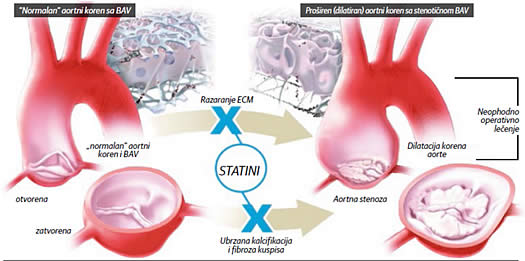

|

Statini svojim antiinflamatornim, imunomodulatornim i snažnim hipolipemijskim sposobnostima mogu uticati na prirodnu progresiju nastanka

komplikacija vezanih za prisustvo BAV delom utičući na usporenje kalkcifikacije aortnih kuspisa I stabilizujući ekstracelularni matriks (ECM ) |

Hirurško lečenje BAV kod odraslih nije neophodno sve do pojave progresije bolesti ili komplikacija koje se inače javljaju u oko 30 odsto slučajeva. Od komplikacija najčešće se javlja bikuspidna aortopatija - proširenje torakalne aorte u vidu dilatacije ili aneurizme. Kod aortne stenoze, bikuspidna aortopatija je posledica poremećene dinamike protoka krvi - poststenotična dilatacija. Novija istraživanja su pokazala da, kod postojanja BAV, promene mogu biti i na ćelijskom nivou - u građi samog zida aorte, uz pojavu smanjene čvrstoće na istezanje, što je nevezano za hemodinamsku leziju. Kod ovih pacijenata postoji povećan rizik za pojavu disekcije (rascepa i krvarenja unutar i duž zida aorte), ili aneurizme (velikog proširenja) zida aorte, te se tokom ispitivanja mora pažljivo proceniti širina proksimalnog dela i luka torakalne aorte. Ukoliko se vremenom ukaže potreba za operativnim lečenjem, širina aorte će odrediti vrstu operacije koja će pacijentu biti predložena.